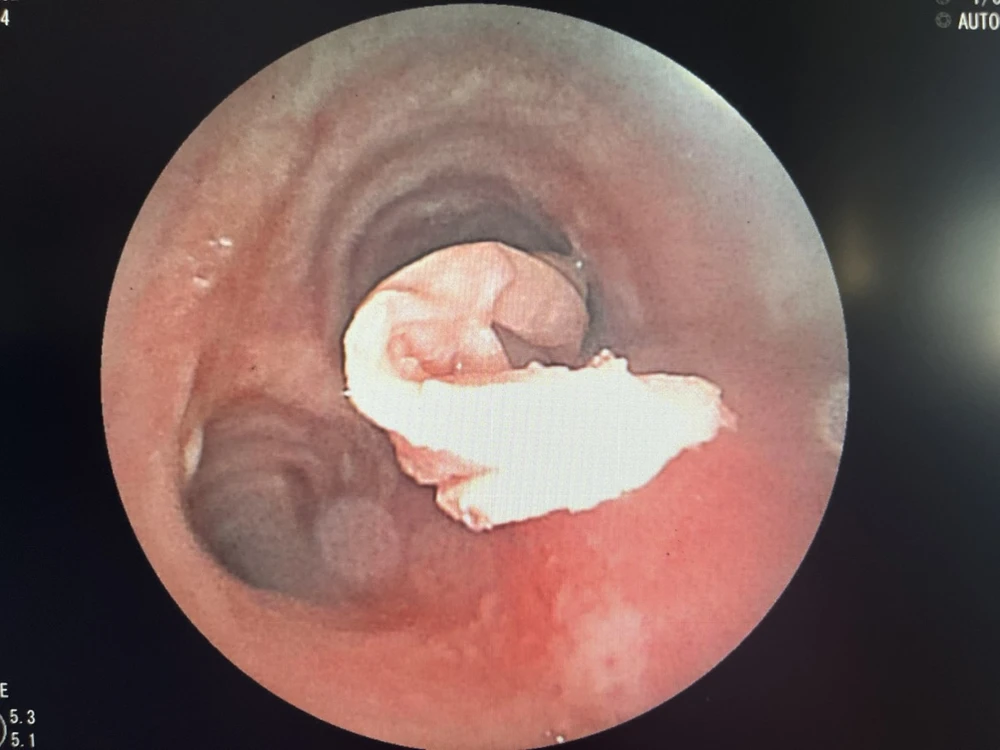

Các các sĩ phải rất nổ lực để nội soi lấy đoạn khăn giấy thấm đầy dịch trong phế quản ra cứu kịp thời bệnh nhân |

Sau đó, êkíp tiếp tục thực hiện nội soi phế quản ống mềm có thực hiện tiền mê, ghi nhận lòng phế quản bên phải có dị vật là đoạn giấy dài chèn bít phần lớn lòng phế quản phải. Đoạn giấy bị thấm dịch ở đường thở đã mềm, việc lấy ra rất khó khăn, các bác sĩ cẩn thận phối hợp kẹp và dụng cụ hút để lấy dị vật.

Sau gần 1 giờ nỗ lực, êkíp nội soi đã lấy thành công dị vật đoạn khăn giấy (được se lại) kích thước khoảng 0,5 x 15cm.